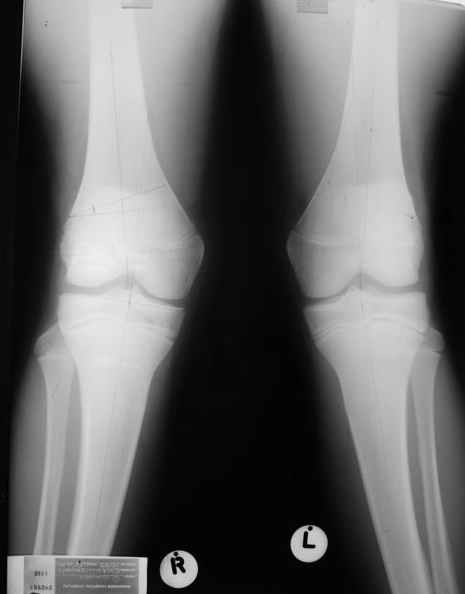

Иммобилизация лонгетной гипсовой повязкой 2 мес. После прекращения иммобилизации, пр начале ЛФК отмечена нарастающая вальгусная деформация конечности. Рентгенограммы в приложении. Хотелось бы узнать Ваши предложения по тактике лечения

Уважаемый Евгений ! Спасибо за ответ, но мне представляется, что в нашем случае основной проблемой является не столько прогрессирующий вальгус конечности, сколько несросшийся перелом мыщелка бедра и дефект мыщелка большеберцой кости - вероятно первичная репозиция выполнялась без пластики.

С учетом всего сказанного - наличия прогессирующего вальгуса конечности, довольно приличного объема движений, имеющегося, вероятно, некроза мыщелка бедра, наиболее рациональным представляется удалить пластину с б\б кости, произвести остеотомию б\б кости с коррекцией вальгуса, разгрузив тем самым наружный отдел сустава, и синтезировать фрагменты голени накостным фиксатором. Максимально тано начать восстановление движений в суставе. Скорее всего рано или поздно речь о протезировании всеже возникнет, но мы хотя бы будем иметь приличную ось конечности.

Тут ситуация совсем другая. Деформация не около-, а самая что ни на есть внутрисуставная. Покорректировать внешний вид конечности путем остеотомии дистального отдела бедра и high tibia (плюс или минус клин, одномоментно-постепенно, аппарат-пластина-стержень - дело третье) не сильно сложно, но это не решение проблемы. У больной, по

сути отсуствует латеральный отдел коленного сустава, что требует костно-пластических вмешательств непосредственно на артикулирующих

поверхностях.